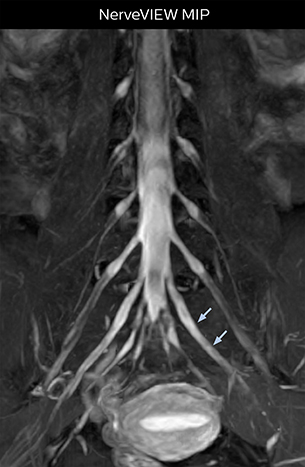

“In such case, we would then browse through axial T2-weighted MR images slice by slice and mentally reconstruct the actual situation based on both radiculography and MRI. Fortunately, NerveVIEW can now very well show nerve courses and presence of nerve compression or edema in one single image series.” “We have often seen NerveVIEW directly depict details of the nerve compression that were not observed by radiculography. Therefore, we think that with NerveVIEW we can reduce the number of invasive examinations, especially for some patients with lumbar plexus symptoms.”

“Before NerveVIEW, diagnosis by MRI alone was sometimes difficult, unless there was a strong suspicion based on clinical symptoms,” says Shoji Yabuki, MD, DMSc, Orthopedic surgeon at Fukushima Medical University School of Medicine. “This is why we routinely perform selective lumbosacral radiculography (nerve root block) and x-ray in such cases. However, radiculography can only depict nerves as far as the contrast agent reaches. When a nerve is distorted by compression, the contrast agent will not pass through this compressed area, preventing us from evaluating the full nerve compression.”

“Although symptoms of typical disc herniation and atypical hernia are very similar, the actual site of herniation is different. It is therefore important to characterize the nerve’s condition both inside and outside of the intervertebral foramina. “Conversely, if we see no abnormality in NerveVIEW, we can assume at least that there is no severe condition that requires surgery. Like this, it can help us avoid unnecessary surgery. NerveVIEW can have a tremendous impact in this way.”

“NerveVIEW is really useful for those cases where a nerve disorder is strongly suspected based on the clinical examination but our regular MRI images do not show any findings. These atypical herniations and spinal canal stenosis, occurring in 5% to 15% of the total lumbar herniation/stenosis cases are our main target when using NerveVIEW,” says Dr. Yabuki.

“NerveVIEW can clearly show nerve courses and presence of nerve compression. However, when multiple abnormalities are seen, it can still be hard to determine which nerve is causing the symptoms,” says Dr. Yabuki. “In our experience so far, we see abnormal findings on NerveVIEW in about 70% of elderly patients. As the pain is usually caused by only one nerve, we thus need to find the exact corresponding nerve.” “With a nerve root block, the patient's pain is improved by infiltration of local anesthesia directly around the nerve root considered to be responsible. Knowing such nerve root block findings prior to image interpretation, helps to easily recognize abnormal findings on NerveVIEW as well. In other words, without a priori knowledge, based on symptoms and/or nerve root block findings, we must be aware of the possibility of overdiagnosis.”